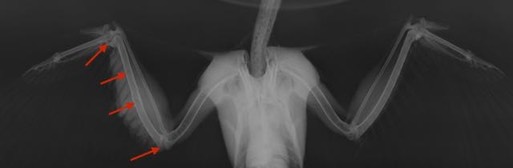

Sharp-shinned Hawk 17-625

We don’t know what this hawk crashed into in Pasco, WA, but in addition to the badly fractured humerus, the elbow and wrist are damaged. I didn’t mark it with an arrow, but the coracoid is also separated from the sternum. The wing was not repairable.